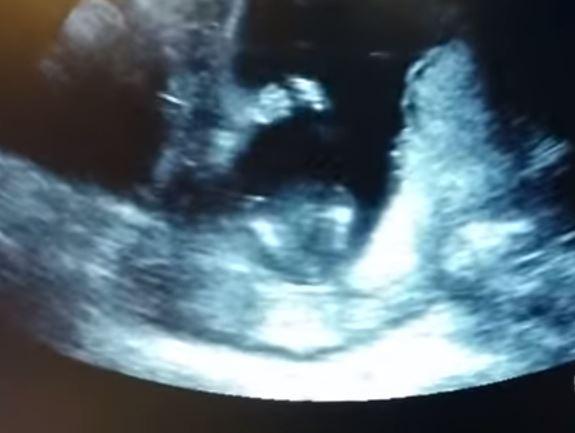

تداولت مواقع اليوم، فيديو لجنين في بريطانيا يصفق داخل رحم أمه، بينما يغني والداه له، وقد حقق الفيديو أكثر من مليوني مشاهدة على موقع "يوتيوب".

وبحسب الفيديو، يظهر الجنين وهو يصفّق على أنغام الأغنية الإنجليزية: "إذا كنت سعيدا صفّق بيديك"، والتي كان والده يغنّيها في إحدى جلسات التصوير بالأمواج فوق الصوتية.